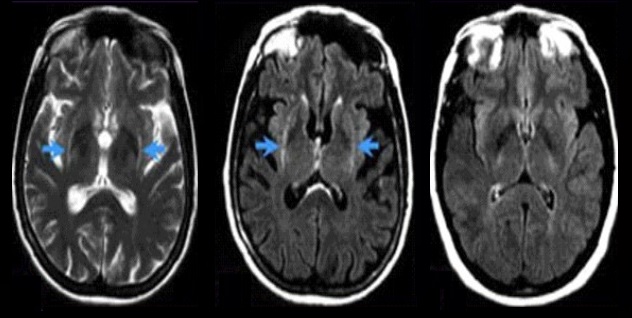

Una vez que se establece el diagnóstico de parkinsonismo se busca la causa del mismo. La etiología es muy variable y normalmente se realizan pruebas de laboratorio y neuroimagen anatómica para descartar causas secundarias como puede ser la toma de ciertos fármacos, las alteraciones hormonales, la presencia de un tumor, la hifrocefalia o una lesión por isquemia cerebral. Si no se encuentra ninguna enfermedad que produzca parkinsonismo de forma secundaria, se habla de un parkinsonismo de origen primario.